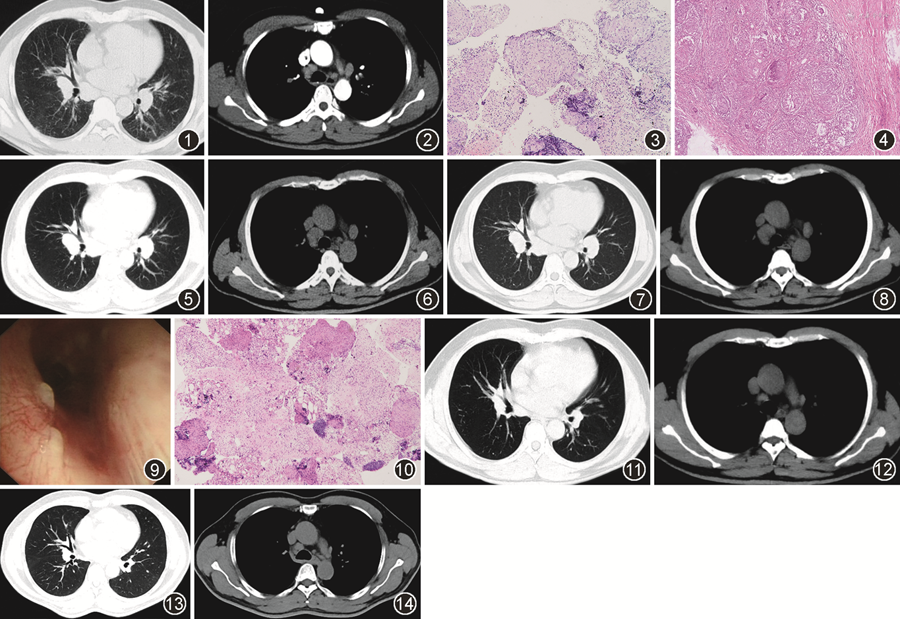

患者男性,52岁,因“呼吸困难2个月,发现皮肤结节1个月”于2016年5月就诊我院呼吸科门诊。2016年3月患者劳累后出现呼吸困难,无发热、咳嗽、咳痰、胸闷等症状。5月4日洗澡时发现双前臂伸侧皮下结节,触之活动,局部无红肿、疼痛及感觉异常。5月14日就诊于当地医院,血常规检查示白细胞为7.55×109/L,中性粒细胞比率为67.6%,血红蛋白及血小板正常;肝肾功能、尿便常规及凝血指标正常;超敏C反应蛋白4.25 mg/L(正常参考值:<8 mg/L)、ESR为5 mm/1 h(正常参考值:<20 mm/1 h);类风湿因子、抗溶血性链球菌O(ASO)、免疫球蛋白3项、补体C3和C4、抗核抗体谱、抗中性粒细胞胞质抗体谱均未见异常。肿瘤标志物中神经元特异性烯醇化酶(NSE)20.9 μg/L(正常参考值:0~16.3 μg/L),其余正常。结核感染T细胞检测(T-SPOT.TB)阴性;血管紧张素转化酶(ACE)81 U/L(正常参考值:0~55 U/L)。PPD试验阴性。肺功能:FEV1占预计值%为89.1%,FEV1/FVC为80%,TLC占预计值%为71.5%,DLCO VA占预计值%为60.3%,考虑为限制性通气障碍伴弥散功能减低。2016年5月14日外院胸部增强CT(图1,2)示双肺门及纵隔淋巴结肿大。

患者于2016年5月30日在我院门诊行第一次支气管镜检查,镜下见黏膜普遍水肿,气道内少量黏稠分泌物,左主支气管远端及左上叶支气管开口可见黏膜多发小结节。N7淋巴结穿刺活检、支气管肺泡灌洗液(BALF)病原学示细菌、真菌涂片及培养阴性,抗酸染色阴性,结核/非结核分枝杆菌培养阴性(-)。BALF细胞分类中淋巴细胞占51%,吞噬细胞49%;CD4+/CD8+ T细胞4.3(参考范围:0.9~2.0)。病理示(左主支气管)黏膜显慢性炎;(N7)涂片见淋巴细胞及上皮样细胞,可见上皮样肉芽肿(图3)。外院超声示双侧前臂上段伸侧皮下脂肪层探及不匀质低回声区,范围42 mm×8 mm(右),25 mm×7 mm(左),26 mm×5 mm(左),边界清,彩色多普勒示其内血流信号丰富。2016年5月17日外院行左侧前臂皮下结节切除术,病理结果(图4)为非干酪样坏死性类上皮肉芽肿,大小较均匀一致,PAS及抗酸染色均为阴性;我院病理科会诊(前臂结节)符合结节病。考虑患者结节病可能性大,6月3日加用泼尼松(30 mg,1次/d)口服,口服1个月后,7月3日减量(25 mg,1次/d),此后建议每10天减半片,患者未遵医嘱减量,继续服用25 mg至2016年9月复诊时。经激素治疗后,自觉呼吸困难好转,右侧前臂皮下结节明显缩小,复查超敏C反应蛋白1.8 mg/L(正常参考值:<8 mg/L),ACE为45 U/L(正常参考值:0~55 U/L)。复查胸部CT(图5,6)可见纵隔肺门多发淋巴结较前增大,最大者短径约18 mm。建议继续泼尼松25 mg规律减量,2个月后复查。2016年11月复诊,右前臂皮下结节消失。胸部CT(图7,8)可见纵隔肺门淋巴结较前进一步增大,最大者短径约21 mm。由于患者在诊断“结节病”服用激素后,皮下结节缩小消失,但纵隔肺门淋巴结进行性增大,结节病诊断存疑,2016年11月11日行第二次支气管镜检查。镜下见右主支气管、右上叶中间段分嵴、右下叶基底段开口等处黏膜多发白色结节(图9),黏膜活检示慢性炎。EBUS-TBNA穿刺N4R和N8淋巴结,淋巴结穿刺涂片镜下见淋巴细胞、上皮样细胞及多核巨细胞;穿刺病理(图10)中见淋巴细胞团及上皮样细胞肉芽肿结节,伴纤维组织增生,未见坏死,特染显示PAS染色(-),抗酸染色(-),六胺银染色(-),符合肉芽肿性病变。右肺中叶外侧段BALF送检病原学涂片、培养均为阴性。因临床不能完全除外合并结核感染,2016年11月8日泼尼松减量为15 mg(1次/d),1周后减量为10 mg(1次/d)维持2个月,于2017年2月停用。同时于2016年11月23日加用四联抗结核治疗。具体为:异烟肼0.3 g(1次/d)+利福平0.45 g(1次/d)+乙胺丁醇0.25 g(3次/d)+吡嗪酰胺0.5 g(3次/d)口服。2016年12月因高尿酸血症停用吡嗪酰胺改为三联抗结核治疗。先后于2017年2、9月及2018年4月(图11,12)复查胸部CT显示纵隔肺门淋巴结进行性缩小。于2018年5月抗结核治疗满18个月后停药。此后患者在呼吸科门诊规律随访,无呼吸道症状,皮肤无结节、皮疹。末次随访时间为2021年10月,胸部CT(图13,14)示纵隔肺门淋巴结大小稳定。

高莉(医学影像科):患者第一份胸部增强CT(2016年5月)显示淋巴结之间相互不融合,增强后亦未见坏死,总体强化不明显,分布对称,符合结节病特点。结节病患者出现淋巴结受累后增强CT可出现强化,提示高炎症状态,对激素反应较好。患者纵隔肺门淋巴结的总体强化不明显,推测可能与炎症状态不高相关。经糖皮质激素治疗后,纵隔及肺门淋巴结较前增大,且密度较前增高。患者后期在加用抗结核治疗后,淋巴结较前逐渐缩小,治疗反应不符合结节病,诊断需要结合临床综合考虑。